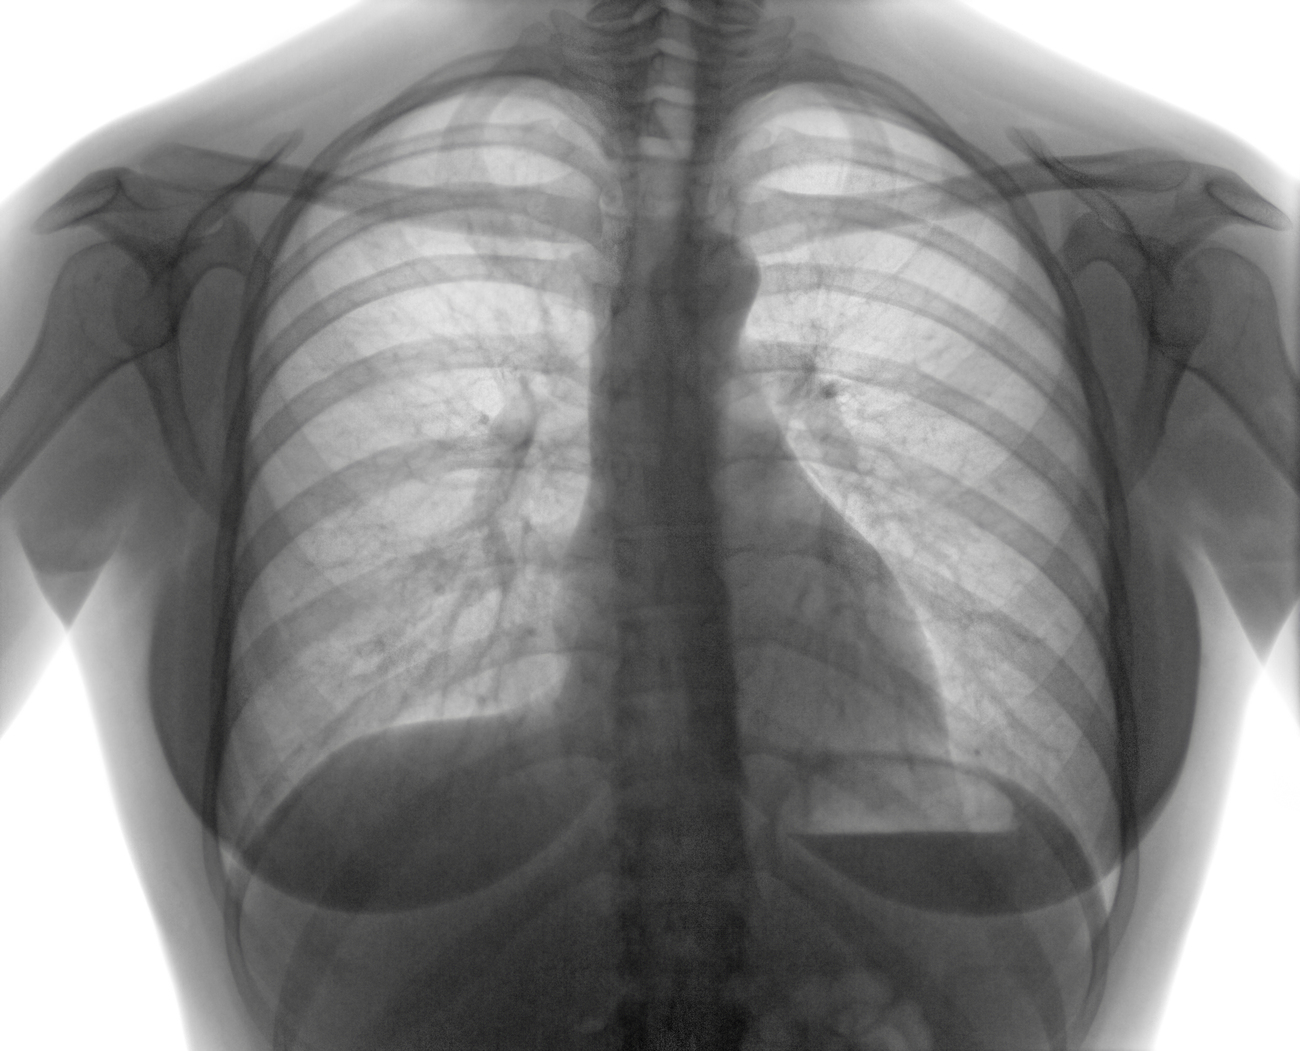

- Rayos X